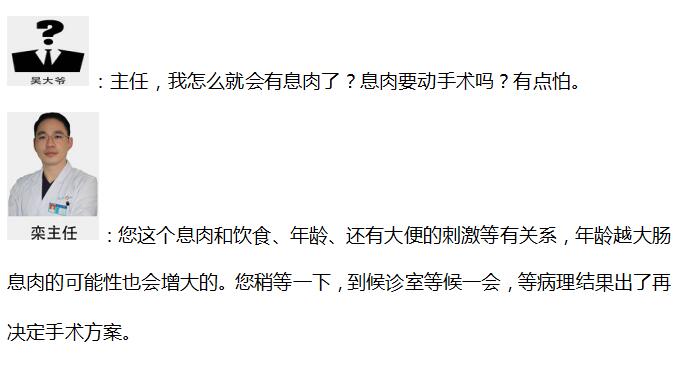

�������ү��Ž��ܳ�����飬���������ж���س�ҽԺ�������ν�����˽���ƽ��������ϰ�ߺ�������ȥ������飬�������ү�������ж�öϢ�⡣���ү��ʱ����ܺ�ڣ�Ϊʲô�����������ҽ����Ա�ĵ绰�����Ķ����ҽ����Աһֱ��ֲ�и�ĸ��Լ���绰���Լ�����Ϊҽ����Ա�ں����Լ�����һֱ��Ϊ�Լ�û�������ϸ����꣬��֢�϶�Ҳ��Զ��!С��Ҳ���ѱ�ס��!

�����������֮�������ʾ���ү�����˳�Ϣ�⣬Ŀǰ��û���ֶ�����